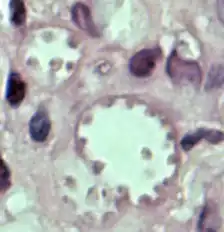

| Leishmania mexicana in a biopsy specimen from a skin lesion stained with H&E. The amastigotes are lining the walls of two vacuoles, a typical arrangement. The species identification was derived from culture followed by isoenzyme analysis. | |